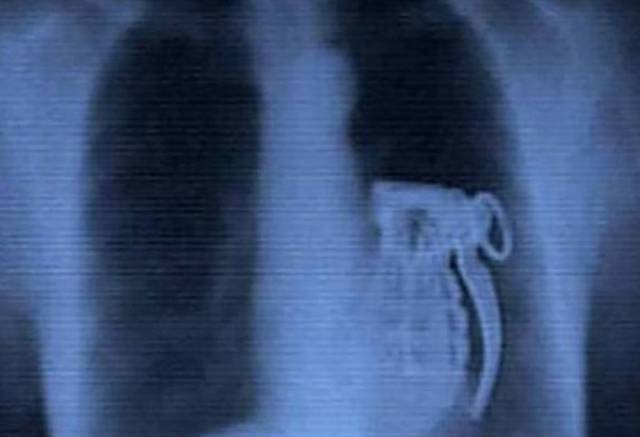

Mit mutat a röntgen?